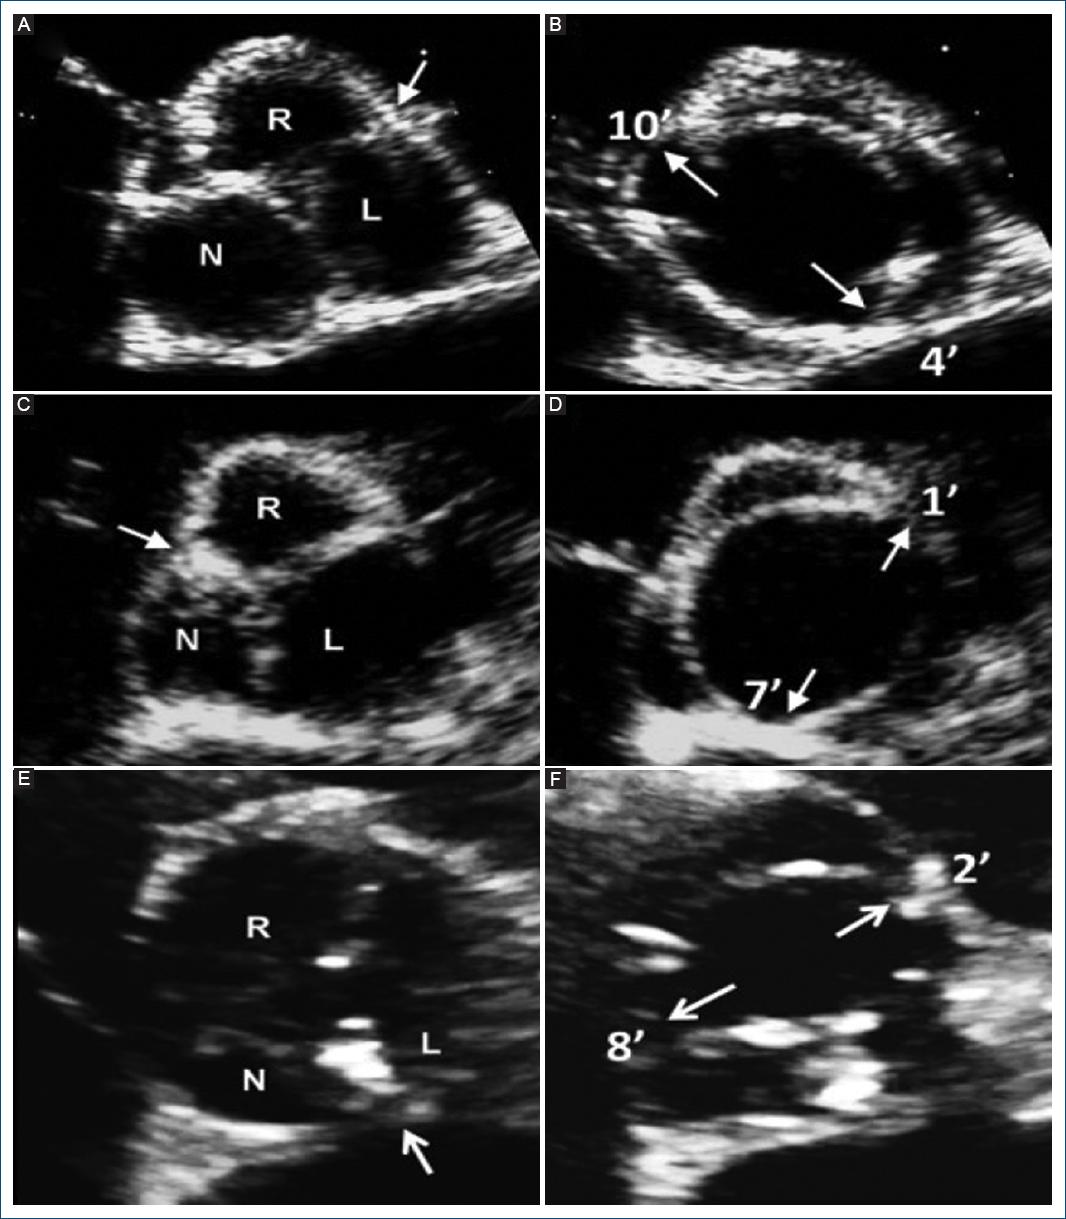

Figura 7 Imágenes de ecocardiografía transtorácica diastólica y sistólica de eje corto paraesternal de los tres fenotipos de la válvula aórtica bicúspide (VAB) fusionada. Aplicable a vistas tomográficas similares obtenidas con tomografía computarizada cardiaca y resonancia magnética cardiaca. A: VAB de tres senos aórticos distinguibles con fusión de cúspide derecha-izquierda, con rafé (flecha) en diástole y B: apertura sistólica típica con comisuras marcadas como la esfera del reloj (flechas). C: VAB de tres senos aórticos distinguibles con fusión derecha-no coronaria, con rafé (flecha) en diástole y D: apertura sistólica típica con comisuras marcadas como la esfera del reloj (flechas). E: VAB de tres senos aórticos distinguibles con fusión izquierda-no coronaria, con rafé (flecha) en diástole y F: apertura sistólica típica con comisuras marcadas como la esfera del reloj (flechas) (modificada de Michelena et al., 201811 con permiso de Elsevier). R: cúspide coronaria derecha; L: cúspide coronaria izquierda; N: cúspide no coronaria.